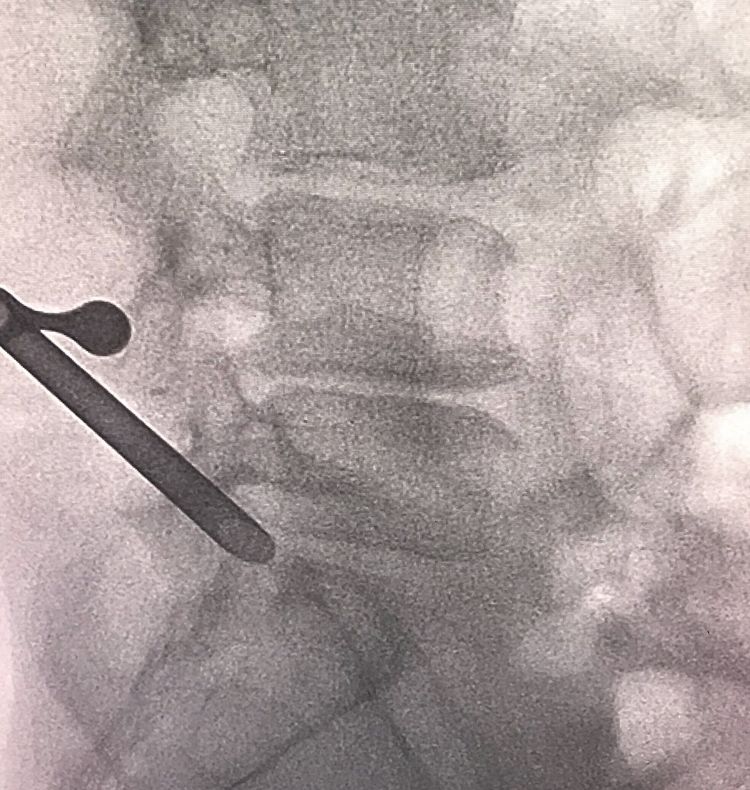

通过人体自然孔道椎间孔,放置工作通道到硬膜囊前间隙突出物靶点,内镜下摘除突出物

被取出的突出物

伤口不到1cm

入院第二天,疼痛科一病区主任王云霞团队为三位患者行“内镜下突出髓核摘除术+嵌压神经根松解术+纤维环修补术”。